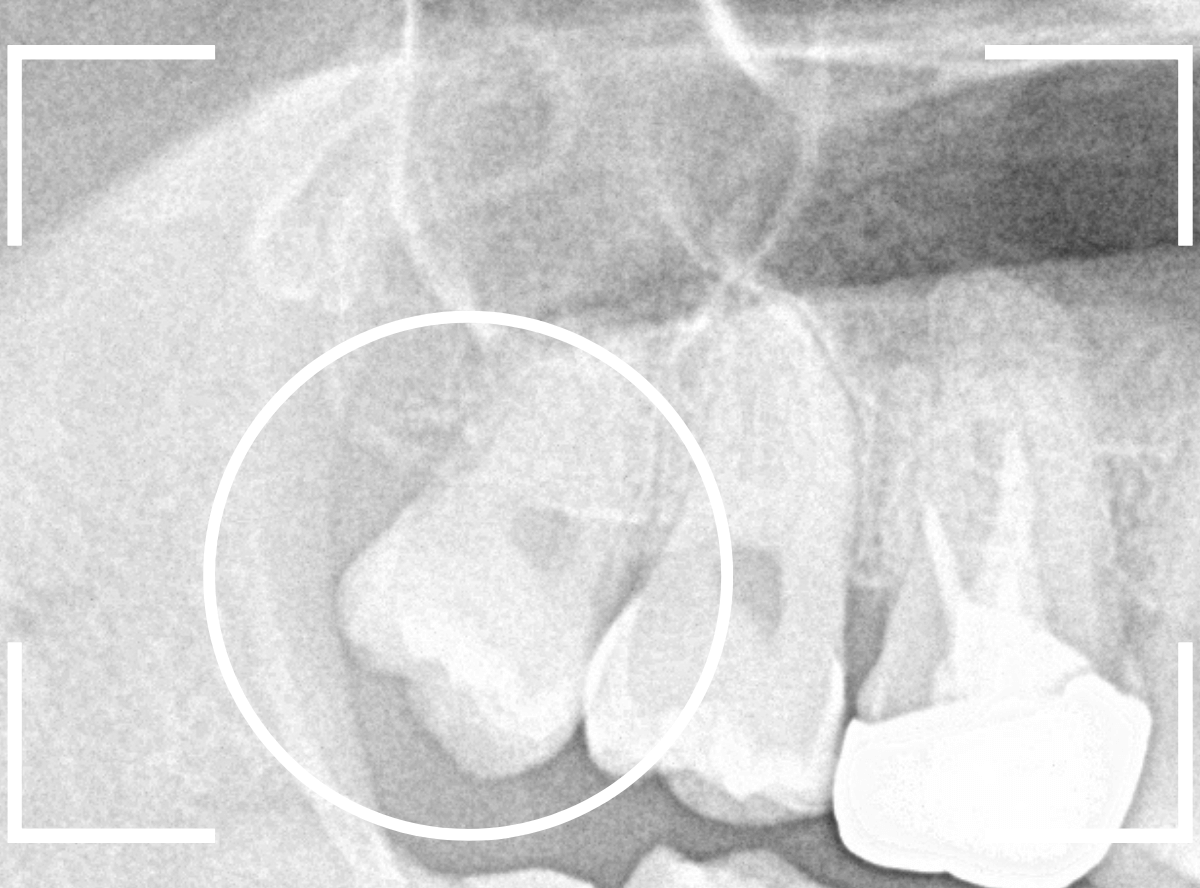

このようなおやしらず、あなたはありませんか?